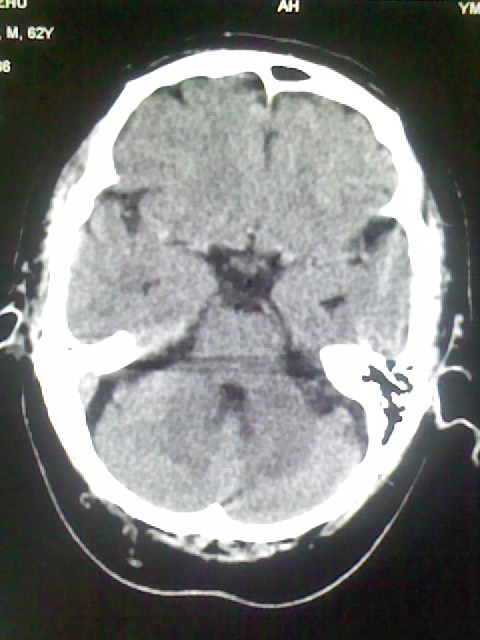

标题: CT15555:头痛 10余日 来诊大家帮忙看看

脑萎缩

脑沟、裂增宽,提法脑萎缩,建议mt检查。

脑萎缩,以小脑为著。

脑沟、裂增宽,提示脑萎缩

老年脑

支持轻度脑萎缩。